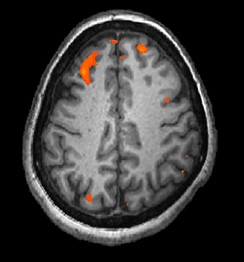

機能的磁気共鳴画像法Functional magnetic resonance imaging (fMRI)

血流と酸素レベルを追跡し、時間の経過に伴う脳活動の変化を表示する。脳の構造のより詳細な画像と、時間の精度を提供する。MRIとfMRIは詳細度が高いため、健康な人の脳と精神障害と診断された人の脳を比較するためによく使用される。